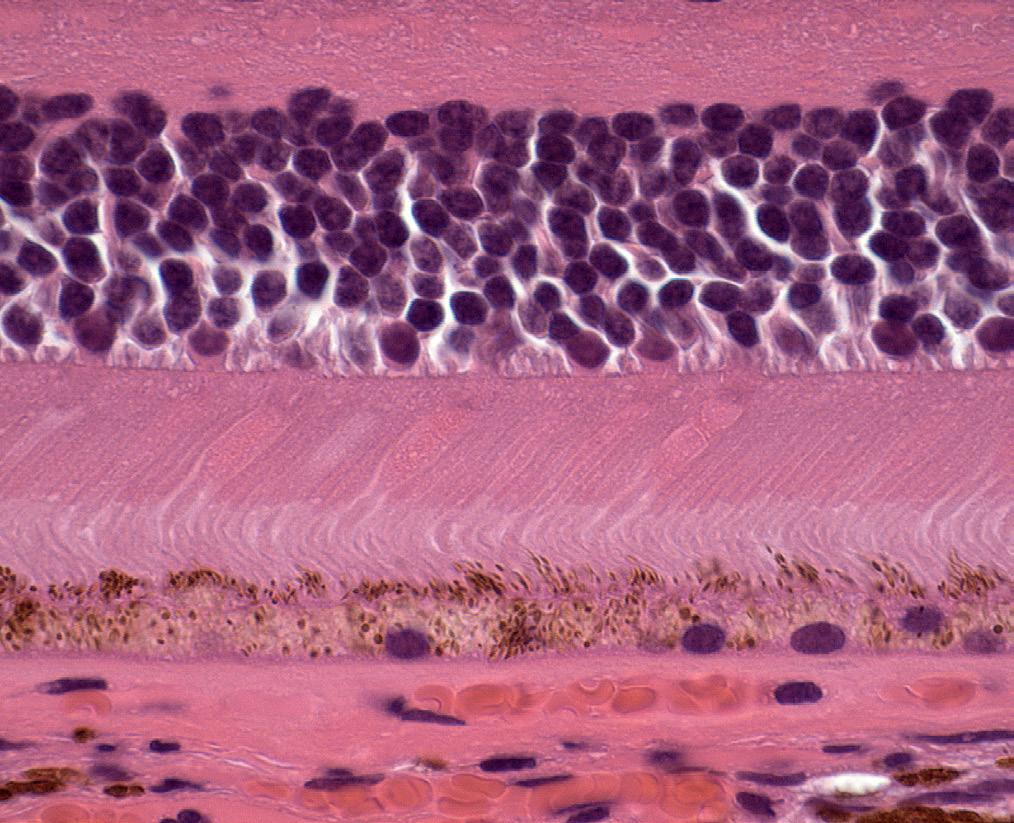

Photo/Electron Micrography

Histology of Outer Retina, RPE & Choroid

Ralph Eagle Jr., MD

Wills Eye Hospital